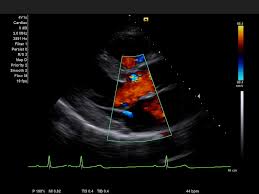

Цветовое допплеровское картирование (Color Doppler), энергетический (Power Doppler) и тканевой допплер (TDI). Эти режимы позволяют проводить как качественную, так и количественную визуализацию гемодинамики.

- Color Doppler обеспечивает наглядное представление направленного кровотока.

- TDI (Tissue Doppler Imaging) используется в кардиологии для анализа движения миокарда, оценки диастолической функции и синхронности.

- Кардиологические расчеты. Система включает специализированные модули для количественного анализа функции миокарда, расчетов ударного объема, фракции выброса и прочих показателей, необходимых при исследовании как взрослого, так и детского сердца. Наличие тканевого допплера (TDI) и M-режима позволяют выполнять полноценную функциональную эхокардиографию.